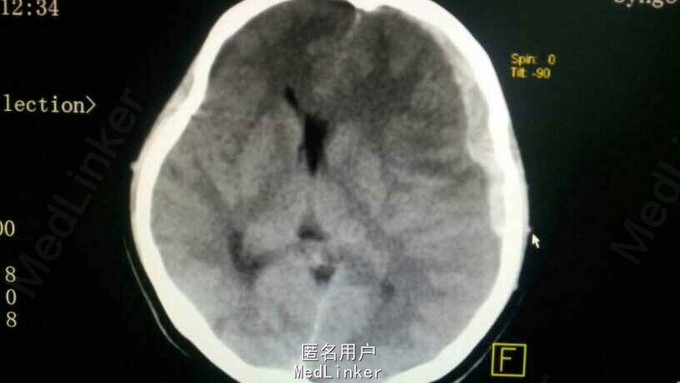

头部摔伤后1小时 患者因从约一米高处坠落,右枕部着地,意识不清3分钟,醒后恶心、呕吐,抽搐,急来诊。

查体:刺痛睁眼,回答错误,刺痛定位,评分2+4+5;意识模糊,右枕部见一头皮血肿;瞳孔左:右为3.0:3.0,光反射灵敏;右侧肢体肌力4级!

诊断:继发性脑干损伤,左侧额颞顶部急性硬膜下血肿,右侧颞骨骨折,外伤性蛛网膜下腔出血,右枕部头皮血肿。 治疗:急诊给予开颅血肿清除及去骨瓣减压术,术中取左侧额颞顶标准大骨瓣,术中见左侧颞叶脑挫裂伤,外侧裂皮层血管出血,脑膨出逐渐加重,静点甘露醇和切除部分颞极减压后迅速缝合。术中血压一直尚可,术终血压下降,70/45左右,呼吸微弱20左右,心率75左右,指脉氧100,未能复查头颅CT,速返病房抢救,给予多巴胺维持治疗16小时后,患者偶发呼吸暂停,呼吸机治疗后患者家属放弃治疗,回家!

术前对病情估计不足,30多毫升血导致中线明显移位,脑肿涨明显,应该向家属交待预后差!